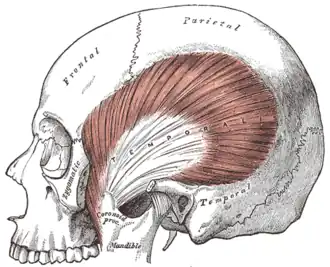

The temporalis muscle; the zygomatic arch and masseter have been removed. | |

In anatomy, the temporalis muscle, also known as the temporal muscle, is one of the muscles of mastication (chewing). It is a broad, fan-shaped convergent muscle on each side of the head that fills the temporal fossa, superior to the zygomatic arch so it covers much of the temporal bone.[1] Temporal refers to the head's temples.

In humans, the temporalis muscle arises from the temporal fossa and the deep part of temporal fascia. This is a very broad area of attachment.[2] It passes medial to the zygomatic arch. It forms a tendon which inserts onto the coronoid process of the mandible, with its insertion extending into the retromolar fossa posterior to the most distal mandibular molar.[3] In other mammals, the muscle usually spans the dorsal part of the skull all the way up to the medial line. There, it may be attached to a sagittal crest, as can be seen in early hominins such as Paranthropus aethiopicus.